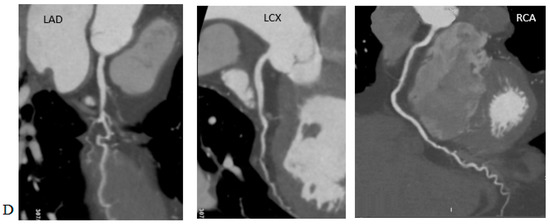

Radiation Doses in Cardiovascular Computed Tomography

by Bartłomiej Kędzierski, Piotr Macek, Barbara Dziadkowiec-Macek, Krystian Truszkiewicz, Rafał Poręba and Paweł Gać

Life 2023, 13(4), 990; https://doi.org/10.3390/life13040990 - 11 Apr 2023

We discussed the contemporary views on the effects of ionising radiation on living organisms and the process of estimating radiation doses in CT examinations and the definitions of the CTDI, CTDIvol, DLP, SSDE, ED. We reviewed the reports from large analyses on the [...] Read more.

We discussed the contemporary views on the effects of ionising radiation on living organisms and the process of estimating radiation doses in CT examinations and the definitions of the CTDI, CTDIvol, DLP, SSDE, ED. We reviewed the reports from large analyses on the radiation doses in CT examinations of the coronary arteries prior to TAVI procedures, including the CRESCENT, PROTECTION, German Cardiac CT Registry studies. These studies were carried out over the last 10 years and can help confront the daily practice of performing cardiovascular CT examinations in most centres. The reference dose levels for these examinations were also collected. The methods to optimise the radiation dose included tube voltage reduction, ECG-monitored tube current modulation, iterative and deep learning reconstruction techniques, a reduction in the scan range, prospective study protocols, automatic exposure control, heart rate control, rational use of the calcium score, multi-slices and dual-source and wide-field tomography. We also present the studies that indicated the need to raise the organ conversion factor for cardiovascular studies from the 0.014–0.017 mSv/mGy*cm used for chest studies to date to a value of 0.0264–0.03 mSv/mGy*cm. Full article